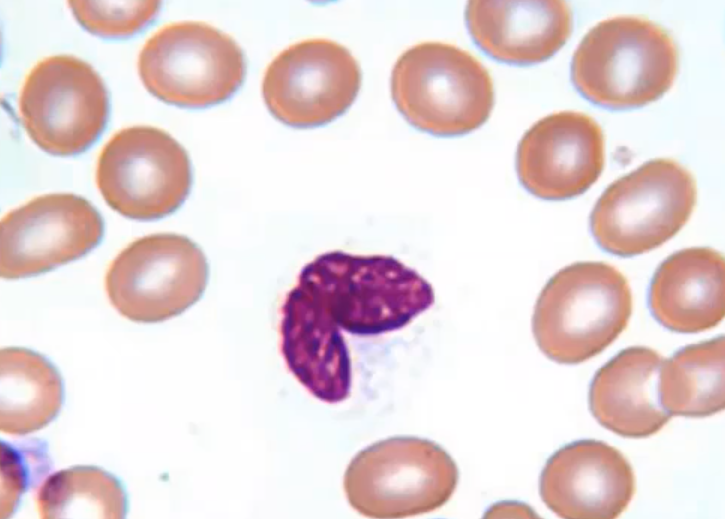

Name

Eosinophil

Rare in blood smears (0-5%)

allergen phagocytosis, reduces inflammation from histamines